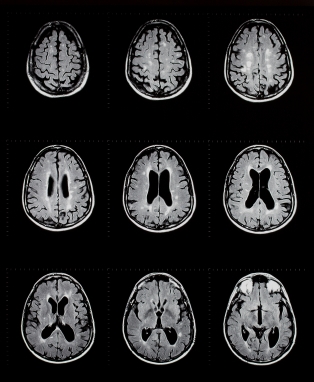

Врач собирает анамнез болезни, выслушивает и изучает жалобы больного, назначает лабораторные и инструментальные исследования: МРТ, исследование электрической активности мозга (измерение вызванных потенциалов), спинномозговая пункция, исследование спинномозговой жидкости.

Медицинские процедуры, проводимые при заболевании рассеянный склероз: Консультация невропатолога, Консультация офтальмолога, Спиральная компьютерная томография, Магнитно-резонансная томография, Спинальная пункция, Исследование спинномозговой жидкости